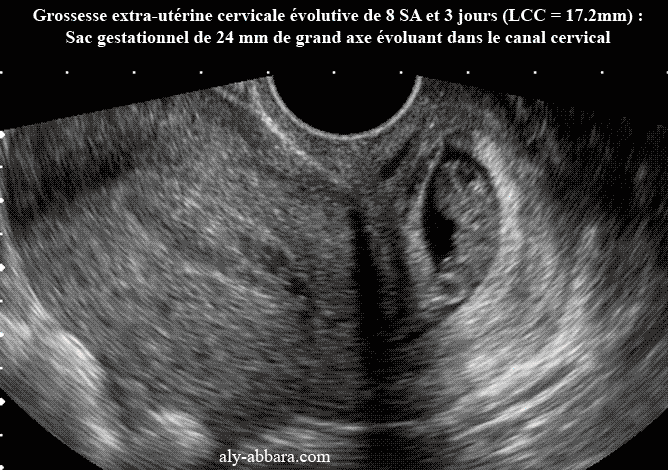

Grossesse extra-utérine cervicale, évolutive de 8 SA et 3 jours

Grossesse extra-utérine cervicale évolutive de 8 SA et 3 jours (LCC = 17.2mm) :

Sac gestationnel de 24 mm de grand axe évoluant dans le canal cervical

(se manifestant cliniquement

par légère métrorragie).

Évolution ultérieure : administration de Méthotrexate et de RU 486, arrêt de l'activité

cardiaque embryonnaire 48 heures plus tard, puis curetage-aspiration simple,à J4

(suite opératoire simple).